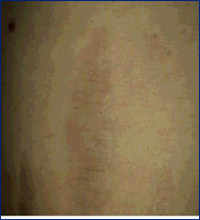

Outros usos incluem tratamento de estrias

(pré e pós tratamento,

8 sessões)